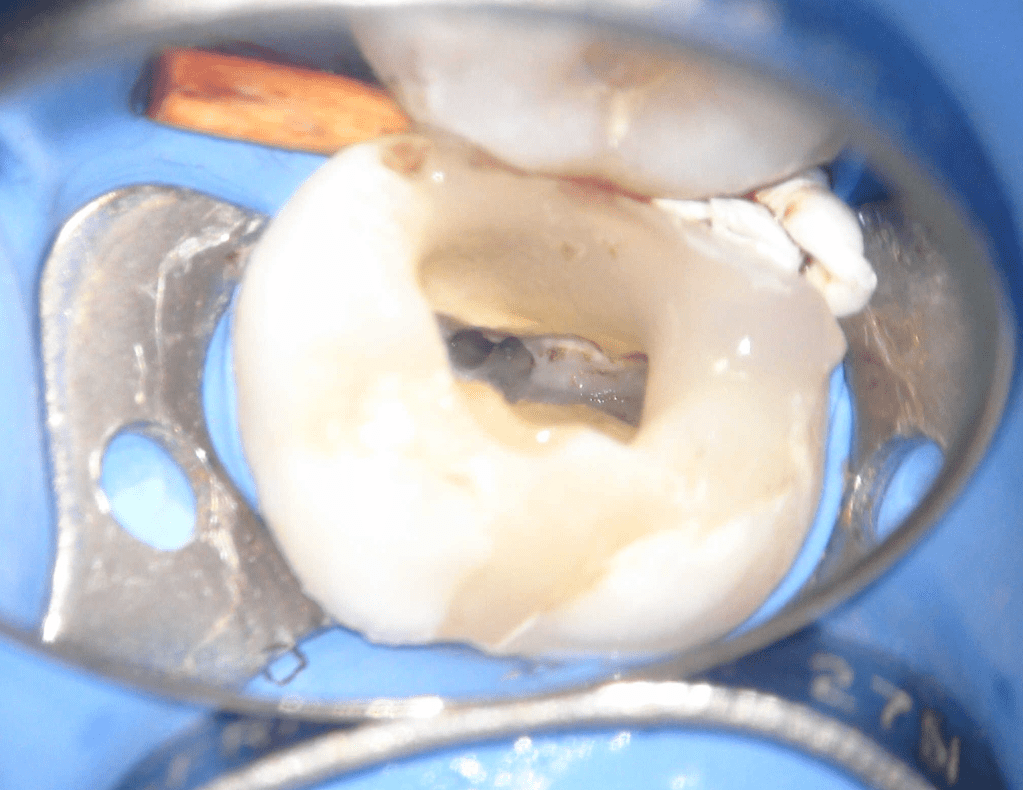

Reco pared vesticular